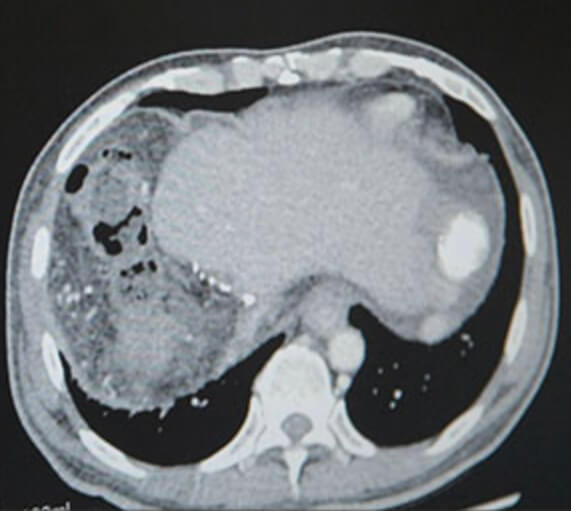

암과 2/3 이상 절제로 제 기능을 하지 못하는 간, 최근 의식을 잃어 생사를 오가는 일이 잦아졌습니다. 아빠는 아픈 딸을 챙겨주고 싶지만 오히려 보살핌을 받아야 합니다.